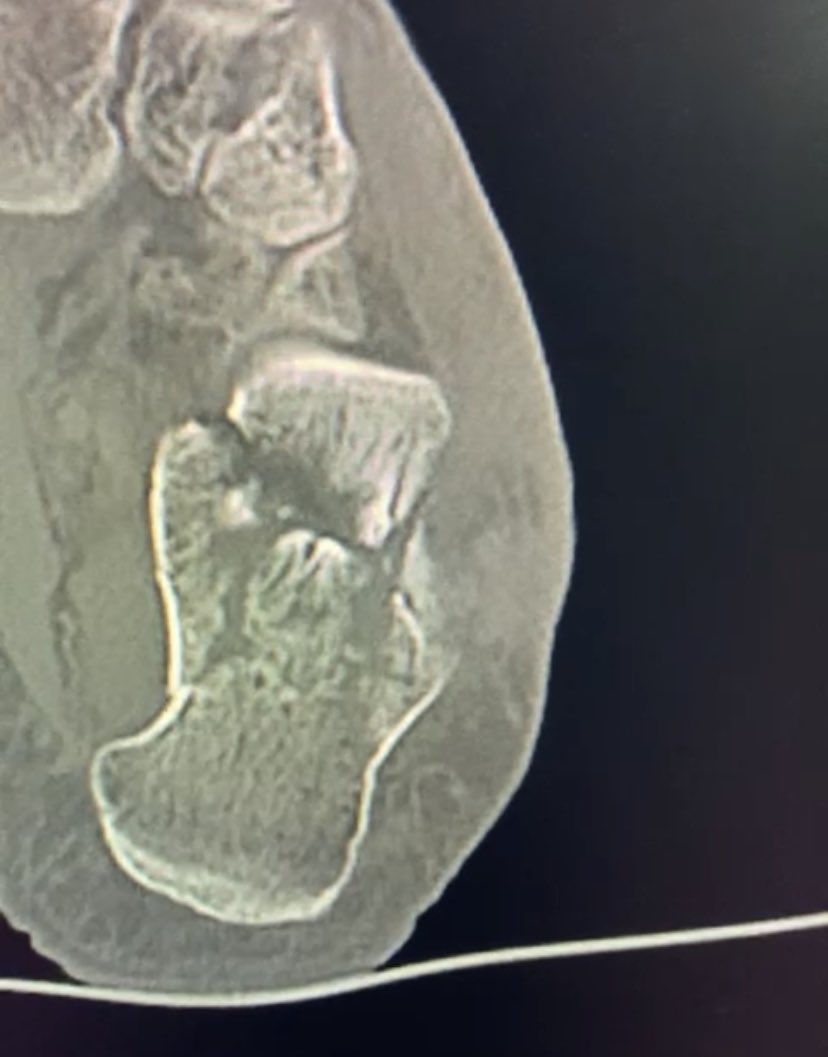

Male 40yo, healthy and physically active.

How do you treat this fracture?

Nonop, ORIF with plate or nailing?

@InvictaOrtho @traumaticum @rkh_md @Gnomelover1970 @aqueipot @DrMarecek

@DrBhavinJadav

#orthotwitter